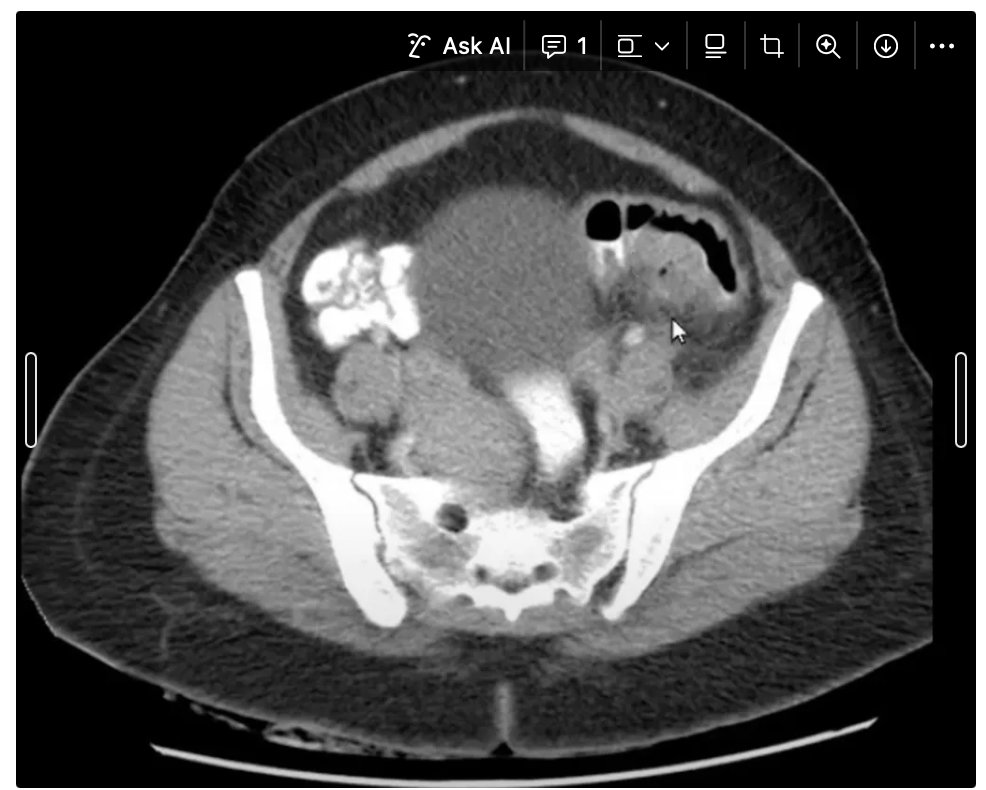

14

Q

Achado?

A

VÁRIOS DIVERTÍCULOS EM COLON DE PAREDE ESPESSADA E BORRAMENTO DE GORDURA

How well did you know this?